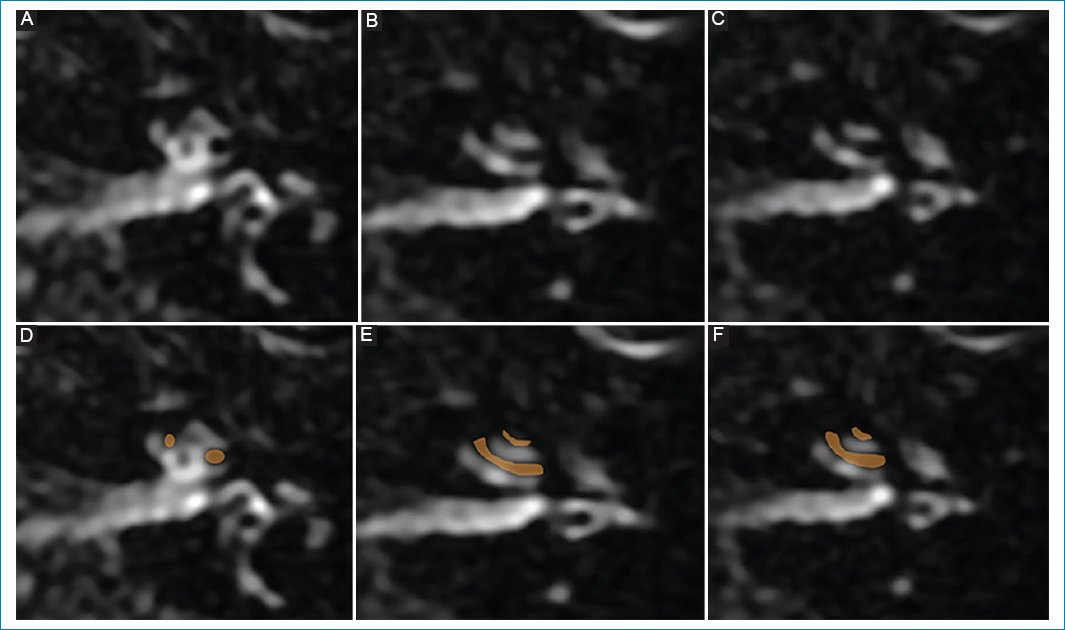

Se realizó RM de cerebro con protocolo para hidrops, observándose hallazgos sugestivos de hidrops coclear derecho de grado I (Fig. 3).

Figura 3. (A, B y C) Hidrops coclear de grado I: dilatación nodular de la escala media, vistas de superior a inferior; representación esquemática en D, E y F.